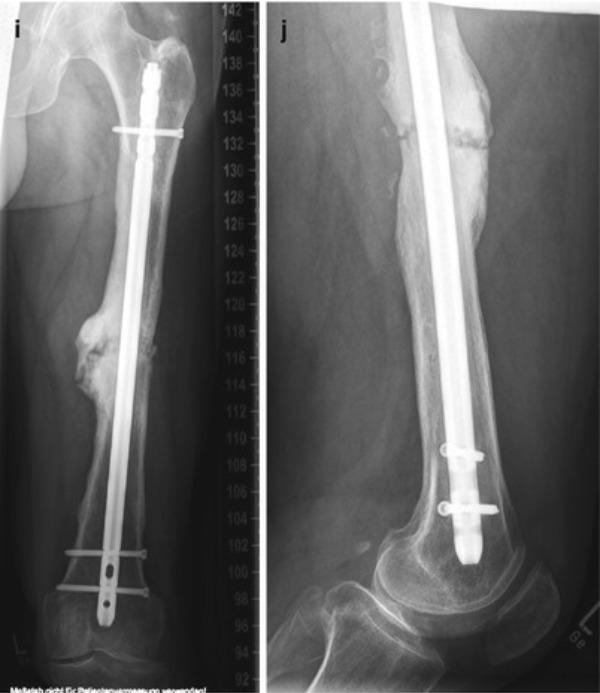

Total Knee Replacement

Total Knee Replacement in Jaipur – The Derma Joint Co Knee pain from severe arthritis, injury, or degeneration can significantly affect mobility and quality of life. Total knee replacement (TKR) is a highly effective surgical procedure that replaces damaged knee joint surfaces with advanced prosthetics, restoring function and reducing pain. At The Derma Joint Co, recognized as the best total knee replacement surgeon in Jaipur, we provide expert care, advanced surgical techniques, and personalized treatment plans to help patients regain mobility and independence. What is Total Knee Replacement? Total knee replacement involves removing damaged cartilage and bone from the knee joint and replacing it with a durable prosthetic implant. This procedure is recommended for: Severe osteoarthritis Rheumatoid arthritis Post-traumatic arthritis Deformities or loss of knee function due to injury or disease Symptoms Indicating the Need for Total Knee Replacement Severe, persistent knee pain affecting daily activities Stiffness and limited range of motion Swelling or tenderness in the knee joint Difficulty walking, climbing stairs, or standing for long periods Chronic knee pain not relieved by medications or physiotherapy Advanced Total Knee Replacement at The Derma Joint Co At The Derma Joint Co, we provide comprehensive care for total knee replacement: Accurate Diagnosis – clinical evaluation, X-rays, and MRI scans Customized Surgical Planning – tailored prosthesis selection and surgical approach Advanced Surgical Techniques – precise implant placement for optimal alignment and longevity Post-Surgery Rehabilitation – physiotherapy and exercises to restore mobility and strength Long-Term Monitoring – regular follow-ups to ensure implant function and prevent complications Why Choose The Derma Joint Co for Total Knee Replacement in Jaipur? Experienced orthopedic and knee replacement surgeons State-of-the-art surgical facilities and tools Personalized treatment plans based on patient’s anatomy and condition Safe, hygienic, and patient-focused clinic environment Trusted as the best total knee replacement surgeon in Jaipur Tips for Faster Recovery Follow physiotherapy and post-surgery exercise programs Maintain a balanced diet rich in protein and calcium Avoid high-impact activities during early recovery Attend all follow-up appointments for monitoring and evaluation Gradually resume mobility under professional guidance Conclusion Total knee replacement is a reliable solution to relieve pain, improve mobility, and enhance quality of life. At The Derma Joint Co – the best total knee replacement surgeon in Jaipur, we provide expert surgical care, personalized rehabilitation, and dedicated follow-up to ensure optimal outcomes. 👉 Book your consultation today at The Derma Joint Co and get specialized care for total knee replacement.